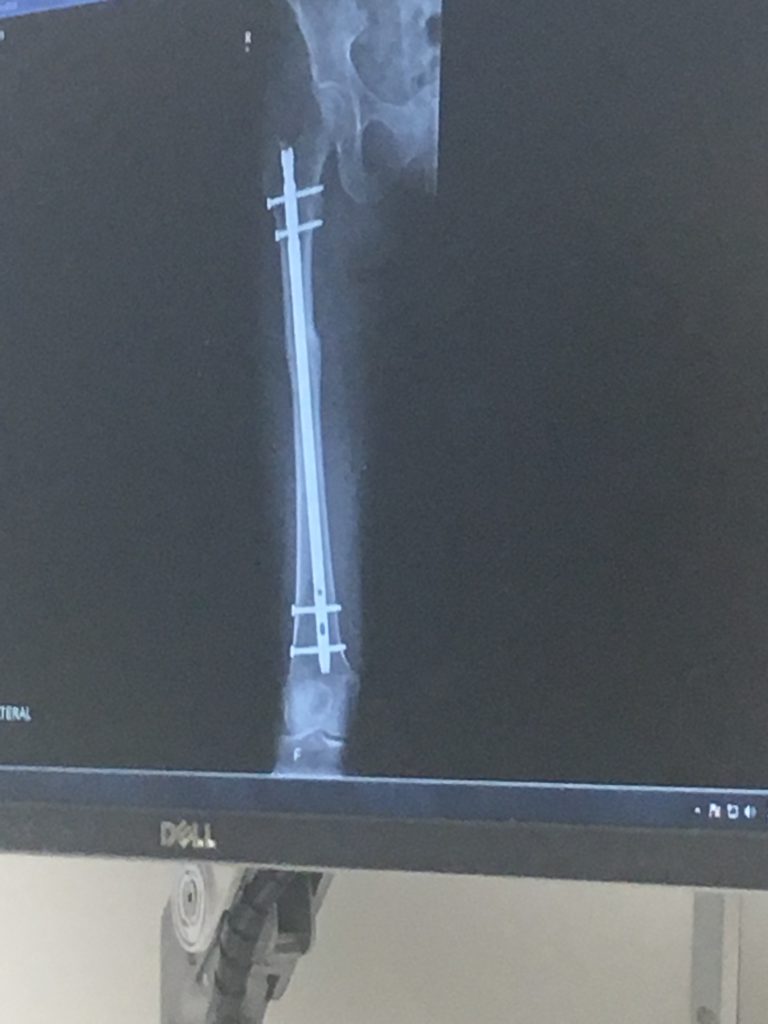

I met Dr. David Wellman, who would perform the surgery with Dr. Ranawat. Together, they repaired my labrum and corrected the ante version of my femur. I stayed at HSS for 2 nights and headed home for months of PT.